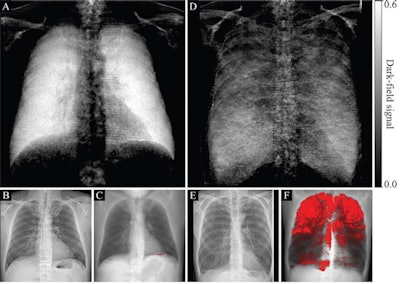

(A, D) Dark-field radiographs, (B, E) attenuation-based radiographs, and (C, F) projections of CT-based emphysema quantification in a healthy 33-year-old man with an emphysema index of 0.1% (A-C) and a 65-year-old man with an emphysema index of 26% (D-F). The same window settings were applied within the respective modality. In B, no abnormalities are apparent. In E, flattened hemidiaphragms and an irregular area of radiolucency are visible. While the dark-field chest radiograph of the healthy subject with no emphysema in the CT-based emphysema projection exhibits a strong homogeneous dark-field signal, the dark-field signal intensity of the subject with pulmonary emphysema appears decreased overall and exhibits an inhomogeneous patchy pattern, corresponding well to the emphysema intensity in the CT-based projection (red overlay, F). Image courtesy of Radiology.The researchers found that locations of focal signal intensity loss on dark-field images corresponded well with emphysematous areas found on CT images. The quantitative analysis showed the dark-field coefficient was negatively correlated with the CT-based emphysema index for all participants (r = -0.54; p < 0.001), the group wrote.